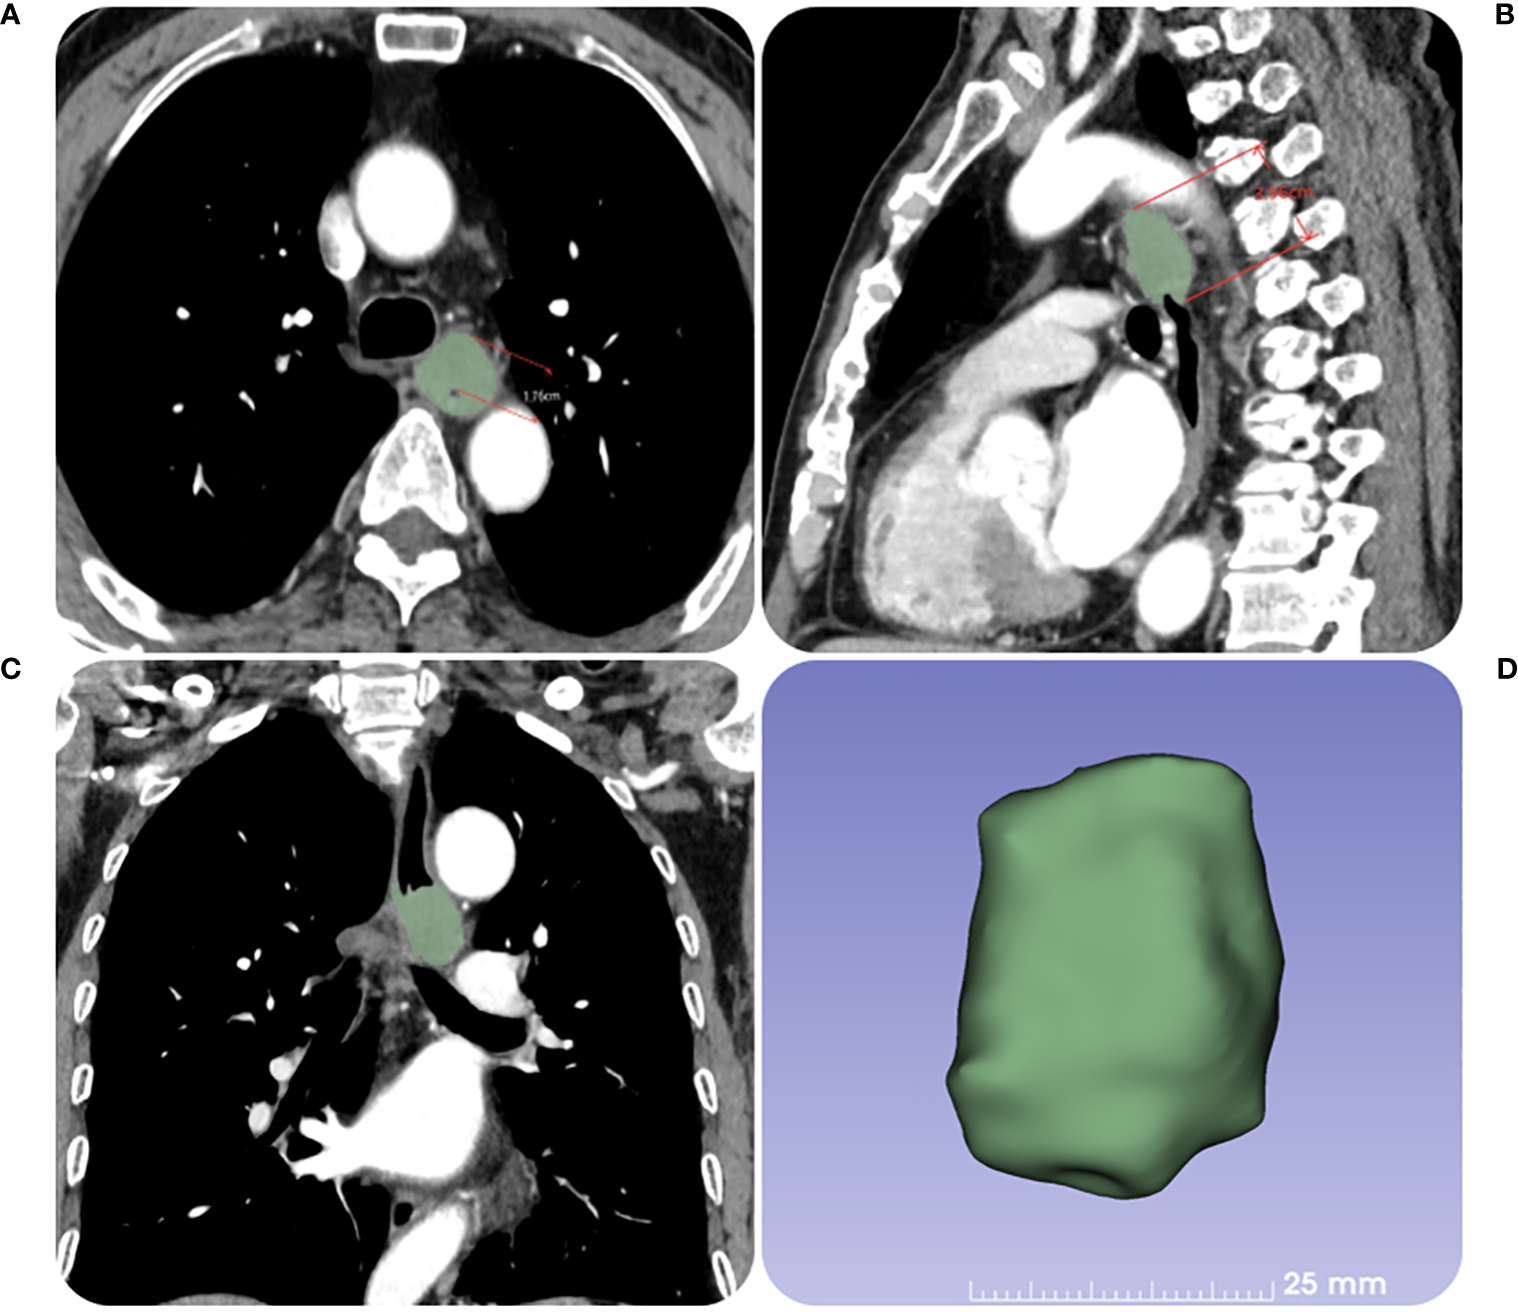

Figure 2

The contrast-enhanced CT images of a 67-year-old female patient with ESCC before RT. (A) The tumor maximal wall thickness is measured in the transverse axial position. (B, C) The tumor length is measured in the sagittal position with reference to the coronal position. (D) The tumor volume is obtained by outlining the tumor layer by layer.

The Radiant DICOM viewer (free software; available online at https://www.radiantviewer.com) was used to upload the thin-slice CECT pictures. The entire tumor was displayed to the greatest extent possible in the sagittal plane using the multi-planar reconstruction mode. The short axis of the biggest lymph node observed in CT images was used to calculate node size, and tumor length was computed based on the axis image. The maximal esophageal wall thickness of the tumor and the short axis of the node at the same level in the area in the transverse section were measured in accordance with the position of the tumor and lymph node before RT. In the transverse slice, a credible tumor region of interest (ROI) was identified within the representative thickened esophageal wall. The software on this image processing workstation automatically calculated the tumor attenuation value. The ROIs covered the largest possible portion of the most noticeably increased area. The tumor’s ulceration and necrosis, gas in the lumen of the tumor, blood vessels, and the adipose around the lesions were all avoided as much as possible when drawing the ROIs. Three sequential tiers of measurements were made. ΔCT value was defined as the relative change of tumor attenuation value before and after RT. All the CT images were analyzed by a radiologist and radiotherapist (with 11 and 12 years of experience, respectively), and when their assessments disagreed, agreement was reached after consultation. The detailed measurement process is shown in Figures 2, 3.